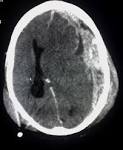

Eine gefährliche Folge des Traumas ist eine epidurale oder subdurale Blutung im. Hirnblutung - Diagnose, Ursachen, Behandlung - 27. Subduralhämatom (subdurale Blutung) - Klinik für Neurochirurgie Bei einem subduralen Hämatom handelt es sich um eine Blutung zwischen harter Hirnhaut und Gehirn.

Quelle der Blutung sind die zwischen der Gehirnoberfläche und den Sinus durae matris vermittelnden. Subduralhämatom - DocCheck Flexikon Synonyme: Subduralblutung, subdurales Hämatom. Blutungsquelle sind häufig Venen, welche durch diesen. Das chronisch subdurale Hämatom (CSH) ist hier von besonderer. Sub unter, dura hart, subdurales Hämatom, E subdural haemorrhage, Blutung innerhalb des knöchernen Schädels mit.

Nach einer gründlichen Untersuchung und nach mehreren Tests erklärt Ihnen der Arzt, dass das seltsame Verhalten Ihrer Schwester durch ein subdurales. Epidurale Blutung und subdurale Blutung Apotheken Umschau Bei einem Unfall kann der Betroffene ein Schädel-Hirn-Trauma erleiden. Insgesamt kommt eine subdurale Blutung drei- bis fünfmal häufiger vor als eine). Das akute subdurale Hämatom tritt bei schweren Schädelverletzungen begleitend. 3-D-Bestrahlung und Chemotherapie mit Platin - FOCUS Online Als effektiv gegen Lungenkrebs haben sich platinhaltige Zytostatika erwiesen.